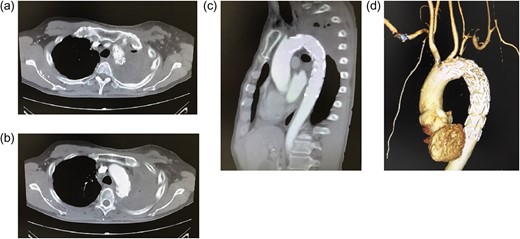

(a) Chest radiography on admission. Consolidation is observed in the left upper lobe. (b–d) Enhanced computed tomography after admission. Extravasation of contrast medium is observed in the distal aortic arch. The entry point is identified distal to the subclavian artery (arrow).